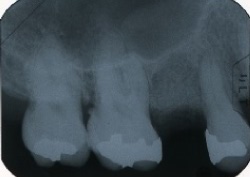

●骨が失われている所は、レントゲンを撮ると黒い影になって写ります。

●エムドゲイン塗布後、徐々に影が、うすくなってきています。